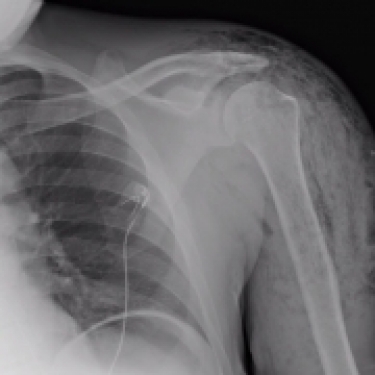

What’s the diagnosis? Gepost op 18 juni 2020 door netwerkvsseh What’s the diagnosis? By Dr. Caroline Blatcher @emdaily.cooperhealth.org Dit delen: Delen op X (Opent in een nieuw venster) X Share op Facebook (Opent in een nieuw venster) Facebook Delen op LinkedIn (Opent in een nieuw venster) LinkedIn E-mail een link naar een vriend (Opent in een nieuw venster) E-mail Afdrukken (Opent in een nieuw venster) Print Vind-ik-leuk Aan het laden... Gerelateerd